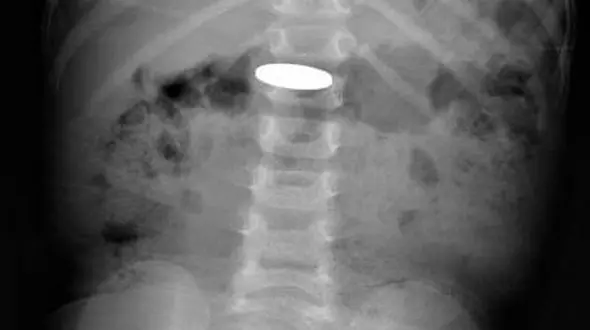

حوادث رکنا: اغلب کودکان از روی کنجکاوی باتریهای سکهای را میبلعند که اثرات آن بسیار هولناک و دلخراش است و باعث سوختن مری آنها میشود.

رکنا: پژوهشگران آمریکایی در بررسی جدیدی دریافتند کودکانی که باتری دکمهای را میبلعند، در معرض آسیب شدید معده قرار دارند.